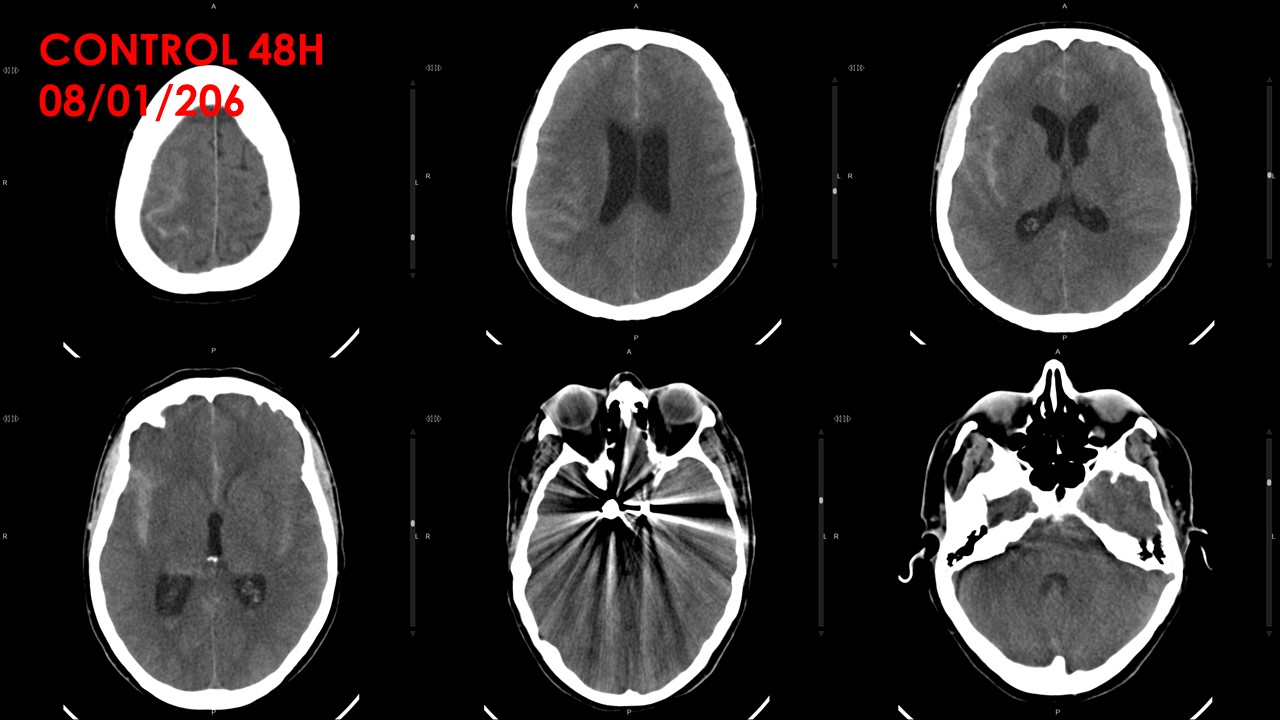

El día 17/1/16 presenta hemiparesia izquierda de instauración brusca. A la valoración, con disartria leve,

hemiparesia facio (moderada)- braquiorcrural (1/5) izquierda, colaboración parcial, latencia de respuesta

alargada, paresia EID 3/5 (colaboración parcial). Se realiza TC craneal urgente que muestra discreto

empeoramiento de hidrocefalia. Posterior al TC presenta mejoría clínica, persistiendo hemiparesia facio

(leve)-braquiocrural 4/5 izquierda, leve disartria (NIHSS 4). Se completa estudio con arteriografía en la que

se objetiva vasoespasmo moderado en ACAD (A2-3), ACMD distal (M3) y en ACAI (A1). Con estos hallazgos, se

administra tratamiento intraarterial con verapamilo bilateral. Se traslada a la Unidad de Ictus para vigilancia

clínica estrecha.

En la Unidad de ictus, normotensa y afebril, con cefalea moderada persistente, buena tolerancia oral, vigil y

orientada, con hemiparesia facio (leve)-braquiocrural (4+/5) izquierda (NIHSS: 1). Se realizan controles por

Doppler que muestran persistencia de vasoespasmo leve- moderado, con mejoría en ACMD. Continuará con

controles cada 24/48 horas para monitorización.

Dada la estabilidad observada, sin otras incidencias a destacar, se traslada a sala de hospitalización de

Neurocirugía, para completar observación.En sala de NRC evoluciona favorablemente sin complicaciones

asociadas. Controles sonograficos y tomográficos muestran estabilidad y resolucion del vasospasmo y

descartan otras alteraciones. Realiza rehabilitacion en sala. Deambula acompañada. Dada la estabilidad

clinica se decide alta domiciliaria.